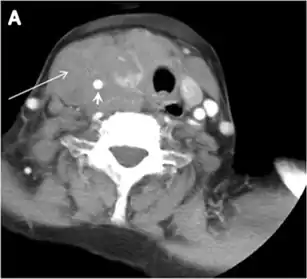

Thyroid lymphoma represents about 5% of thyroid malignancies. Non-Hodgkin's lymphoma is the most common type and can be secondary to generalized lymphoma or a primary tumour. Primary thyroid lymphoma usually pre-exists with Hashimoto's thyroiditis. On CT scans with and without contrast, lymphomas tend to have low attenuation values. Thyroid lymphomas have a variable appearance and mostly manifest as a solitary mass (80%). They may also manifest as multiple nodules (15% to 20%) or as a bulky mass replacing the entire gland with extra-thyroid extension (Figs. 11 and and12).12). The presence of cervical lymphadenopathy supports such a diagnosis. Although it is uncommon, tumour necrosis has been reported.[1]